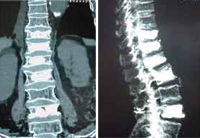

Kyphoplasty with balloon performed on five levelsby Dr. Morgenstern. Female patient with age 80 years, with inmediate erect walking after the intervention. |